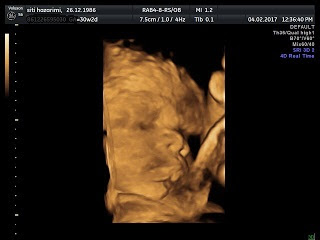

Ilham Mizwar Rizqy, namamu dipilih oleh Babah.

Katanya, Mizwar di tempat kerja seorang engineer. Miszua di sebelah Labu seorang doktor. Jadi, Ibu tidak bantahan untuk nama itu. Bukanlah Ibu nak kamu jadi doktor/jurutera, cumanya nama itu terserlah nama yang baik jadinya. Baik untuk kamu juga nanti, nak, inshaAllah. Rizqy pula diberi kerana dengan kehadiran kamu umpama membuka peluang-peluang rezeki untuk Ibu Babah. Kita ada sebuah rumah untuk berteduh, kita ada lebihan duit tabungan, orang sedekahkan macam-macam untuk kamu. Tak sarat sangat kepala otak Ibu ni nak memikirkan persiapan untuk menyambut kehadiran kamu.

Ilham membawa maksud sumber, inspirasi. Bilamana kakak kamu seorang Ilhamina, maka kamu adalah Ilham kami. As simple as that. ;)